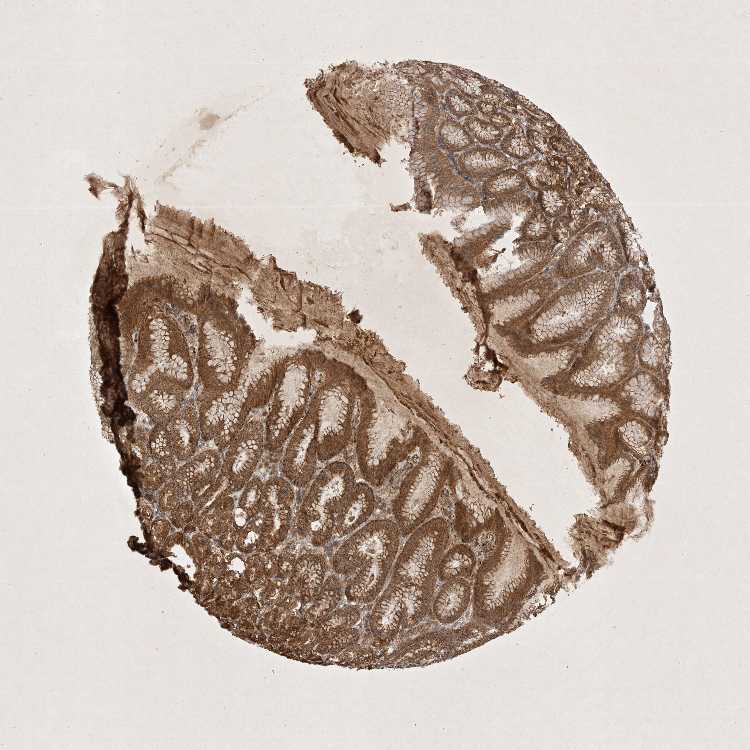

TISSUE PRIMARY DATA STOMACH Show tissue menu

STOMACH 1 - Antibody stainingi

Antibody staining in the annotated cell types in the current human tissue is reported as not detected, low, medium, or high, based on conventional immunohistochemistry profiling in selected tissues. This score is based on the combination of the staining intensity and fraction of stained cells.

Each image is clickable and will lead to virtual microscopy that enables deeper exploration of all samples and also displays staining intensity scores, fraction scores and subcellular localization as well as patient and tissue information for each sample.

Antibody CAB010162Antibody CAB025656

Glandular cells MediumHigh